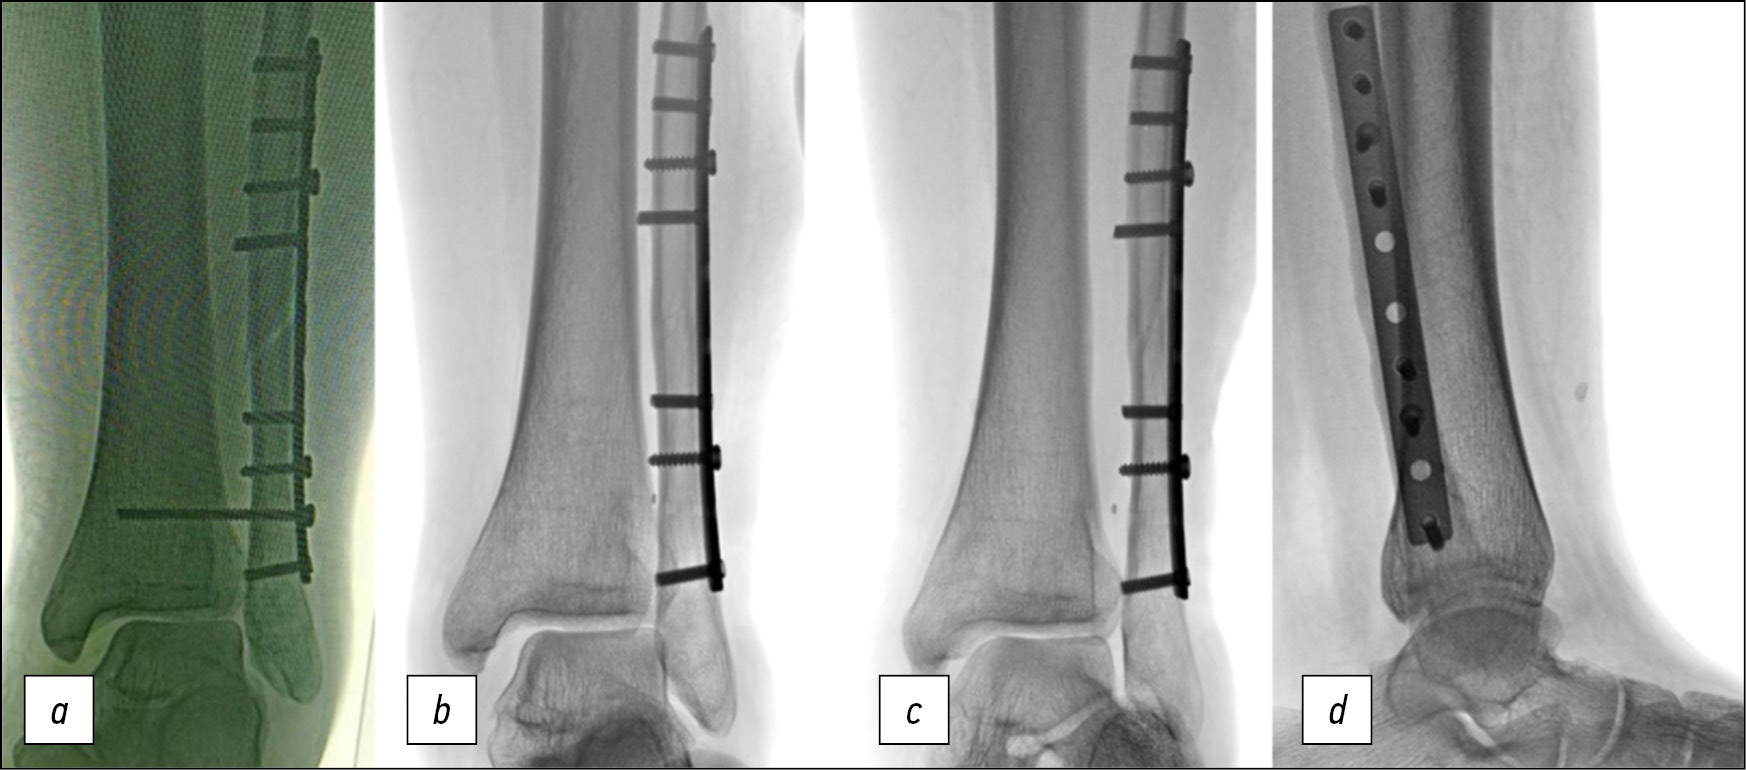

Пациент К., женского пола, 34 года, 328 дней с момента травмы — надсиндесмозного перелома дистальной трети диафиза левой малоберцовой кости, подвывиха стопы кнаружи. Спустя 6 дней после получения травмы выполнено оперативное вмешательство в объёме открытой репозиции и накостного остеосинтеза малоберцовой кости, фиксации дистального межберцового синдесмоза позиционным винтом. На контрольных рентгенограммах диагностирован сохраняющийся наружный подвывих стопы, в связи с чем через 1 месяц после первой операции выполнено повторное вмешательство — перепроведение позиционного винта. Контрольные рентгенограммы после повторного вмешательства демонстрировали сохраняющийся наружный подвывих стопы (рис. 4а). Через 8 недель после повторного вмешательства выполнено удаление позиционного винта. У пациентки сохранялись жалобы, связанные с нестабильностью голеностопного сустава.

Рис. 4. Рентгенограммы пациентки К. после предшествующих оперативных вмешательств: a, b — расширение медиальной щели голеностопного сустава, c — расширение межберцового пространства, d — рентгенограмма в боковой проекции

Fig. 4. X-rays of patient K. after previous surgery: a, b — increased medial clear space, c — increased tibiofibular space, d — lateral X-ray

Рентгенограммы через 6 месяцев после удаления позиционного винта демонстрируют расширение медиальной щели голеностопного сустава (рис. 4b), межберцового пространства (рис. 4c, d).

Лечение

Выполнено оперативное вмешательство в объёме удаления инородных тел, фиксации голеностопного сустава аппаратом Илизарова в шарнирной облегчённой компоновке, фиксации дистального межберцового синдесмоза пуговчатым фиксатором.

Послеоперационные рентгенограммы в прямой (рис. 5a) и боковой (рис. 5b) проекциях демонстрируют восстановление взаимоотношений в голеностопном суставе. На рентгенограммах в боковой проекции (рис. 5c, d) наблюдается ограниченный шарнирными устройствами объём активных движений: подошвенное сгибание (рис. 5c) ограничено 5°. На гониограммах (рис. 5e, f) и подограммах (рис. 5g, h) на 7-е сутки после операции — ходьба без дополнительных средств опоры в условиях внешней фиксации, демонстрирующая наличие сниженного активного тыльного сгибания стопы, умеренной асимметрии при равномерном распределении нагрузки на передний и задний отделы стопы оперированной конечности. Период госпитализации — 14 суток, срок фиксации в аппарате Илизарова — 37 суток.

Рис. 5. a — послеоперационная рентгенограмма пациентки К. в прямой проекции, b — послеоперационная рентгенограмма в боковой проекции, c, d — рентгенограмма в боковой проекции: ограниченный шарнирными устройствами объём активных движений, e, f — гониограммы, g, h — подограммы

Fig. 5. Postoperative X-rays of patient K.: a — A-P-view, b — lateral view, c, d — lateral X-rays demonstrating limited by hinges range of motion, e, f — gait analysis, g, h — computer podography

После демонтажа аппарата Илизарова пациентка не нуждалась в дополнительных средствах опоры и ортопедических изделиях.

Рентгенограммы голеностопного сустава в прямой проекции с внутренней ротацией (стоя с нагрузкой) (рис. 6a) и в боковой проекции (рис. 6b) демонстрируют восстановление взаимоотношений в голеностопном суставе.

Рис. 6. Рентгенограммы пациентки К. после демонтажа аппарата Илизарова: a — в прямой проекции с внутренней ротацией, b — в боковой проекции

Fig. 6. X-rays of patient K. after Ilizarov fixator removal: a — mortise view, b — lateral view

Клинический пример показывает результативность оперативного вмешательства при сокращённых в 2,5 раза сроках фиксации в аппарате Илизарова.